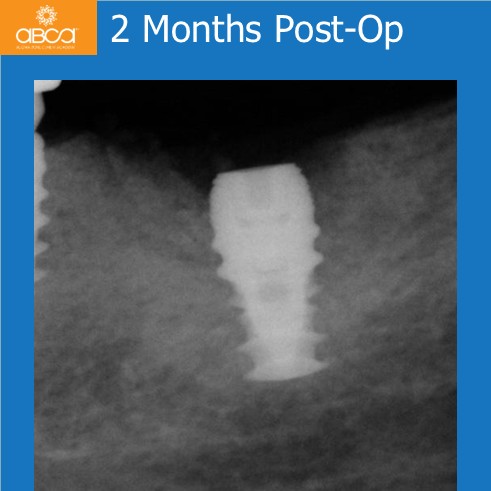

The patient presented with an infected and fractured molar with compromised buccal plate. The extraction was done in segments. Osteotomy prep grafted with Bond Apatite®, uncover osteotomy, immediate implant placement. Note the keratinized gingiva around the healed implant. The key here was no flap at the time of the extraction.